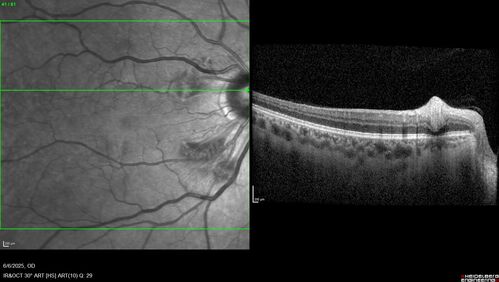

Cotton Wool Spots following cardio-pulmonary bypass

The patient had emergency thoracotomy about 3 weeks ago he had an aortic dissection with a root aneurysm. It had dissected down to the iliacs. The patient had a thoracotomy and aortic valve replacement and large aortic graft.